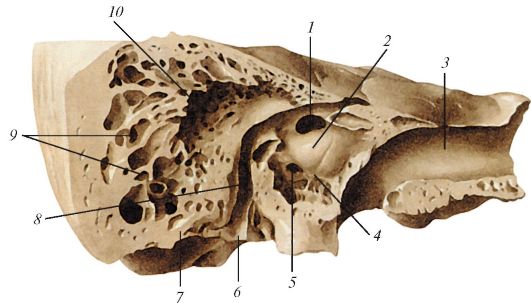

КТ анатомия сосцевидного отростка: особенности и показания